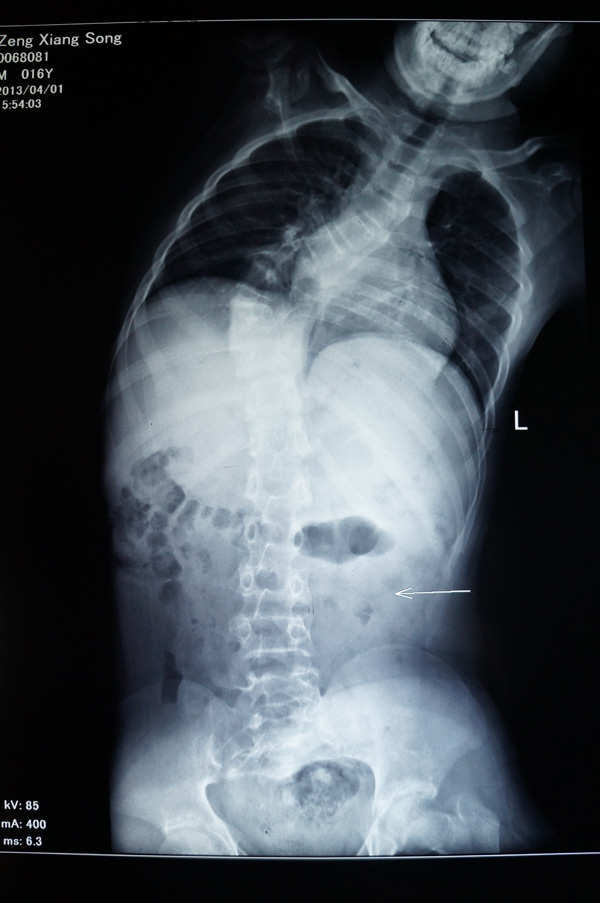

瑞康医院骨脊柱二区的医生给小松做了详细的身体检查,发现他的胸5-腰1椎体节段明显向右侧侧弯,呈小“S”形状,胸5-腰1棘突及棘突两旁无明显压痛及叩击痛,右侧竖脊肌肌张力紧张,左侧正常,站立姿势时测量左侧肩比右侧肩高约2cm。同时进行并足前屈弯腰试验时,发现小松的右侧肩胛骨明显高于左侧,出现“剃刀背”畸形,脊柱左右侧弯柔软性差,Cobb角65°[i],胸腰椎MRI平扫检查确诊:脊椎侧弯畸形。

小松术前的X光片

小松术前的X光片2